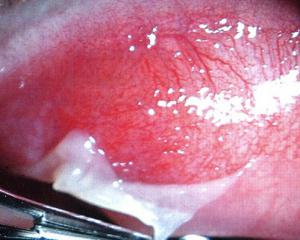

- 2) Фолликулярная форма аденовирусного конъюнктивита характеризуется образованием пузырьковых высыпаний на слизистой оболочке глаза. Фолликулы могут быть небольшие, точечные или крупные, полупрозрачно-студенистыми; находятся в уголках век или могут покрывать всю инфильтрированную и разрыхленную слизистую, больше всего в области переходной складки.

- 3) Примерно в четверти случаев встречается пленчатая форма аденовирусного конъюктивита. При этой форме на слизистой оболочке образуются тоненькие пленки, серовато-белого цвета, они без проблем снимаются ватным тампоном. Осложнением пленчатого аденовирусного конъюнктивита часто является рубцевание слизистой. При пленчатом аденовирусном конъюнктивите страдает общее самочувствие человека: развивается высокая температура (до 38°С–39°С), которая может держаться от 4-х до 11 дней.